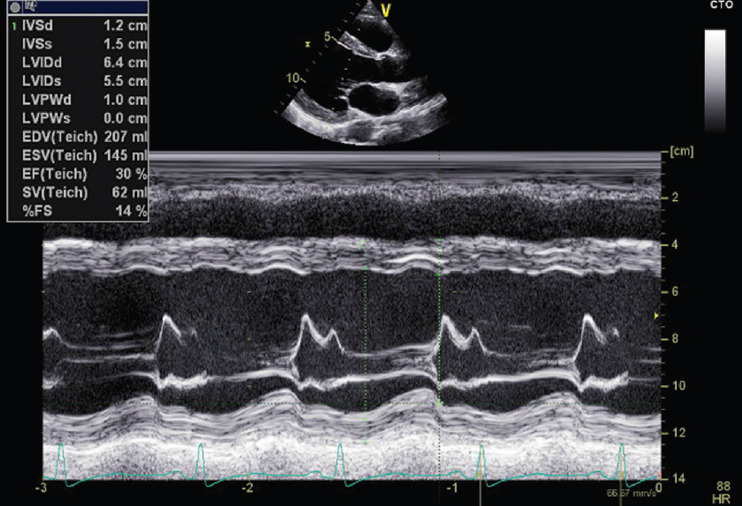

Peripartum cardiomyopathy (PPCM) is a specific form of cardiomyopathy that manifests toward the end of pregnancy or within 5 months postpartum, characterized by a decrease in cardiac output due to impaired myocardial function. This condition has a multifactorial origin, influenced by genetic predispositions, inflammatory processes, autoimmunity, hormonal variations, and nutritional deficiencies. Prognosis varies among patients: while some recover completely within 6 months, others may develop chronic cardiac dysfunction requiring long-term treatment. Vericiguat, a soluble guanylate cyclase stimulator, has shown promising results in the treatment of heart failure with reduced ejection fraction. This drug works by enhancing the nitric oxide signaling pathway, promoting vasodilation, and improving myocardial function. Although the use of vericiguat in PPCM is not yet fully documented, its potential benefits suggest that it may represent a valid therapeutic option when standard therapies are insufficient for symptom control. We present the case of a 32-year-old woman with PPCM, initially undiagnosed, who developed severe symptoms of dyspnea, orthopnea, and peripheral edema postpartum. These symptoms were accompanied by a significant reduction in left ventricular ejection fraction. Following a suboptimal response to standard heart failure therapy, vericiguat was incorporated into her treatment regimen. In subsequent outpatient follow-ups, the patient's symptoms progressively improved, and left ventricular systolic function markedly increased. The patient became asymptomatic and was able to resume her normal daily activities. While this case suggests that vericiguat could be an effective adjunctive treatment for PPCM, it remains unclear whether these improvements were directly attributable to vericiguat or could have occurred with continued standard therapy alone. Further studies are needed to define the role of vericiguat in this condition.

Abstract Image